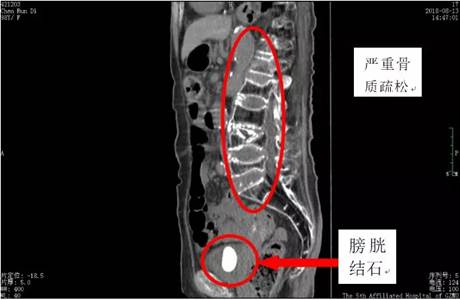

膀胱结石CT片

骨折后长期卧床、近期检查患有膀胱结石,多次去医院就诊却无计可施……近日,广医五院泌尿外科一区迎来了一个99岁高龄的患者。

99岁的黄埔老人陈老奶奶股骨骨折后长期卧床。近3个月来,近来感觉自己反复排尿疼痛不适,并出现尿失禁,生活深受困扰,儿孙们看在眼里,急在心里,后来查出老人家得了膀胱结石,但所到医院均无计可施。经人介绍,在家人的陪伴下,她来到了广州医科大学附属第五医院泌尿外科一区就医。

现在摆在五院泌尿外科专家们面前的难题就是:患者年纪大,患有高血压、冠心病等多种疾病,基础情况不容乐观。患者骨折后长期卧床,导致下肢严重萎缩、严重骨质疏松,围手术期麻醉及手术风险高。